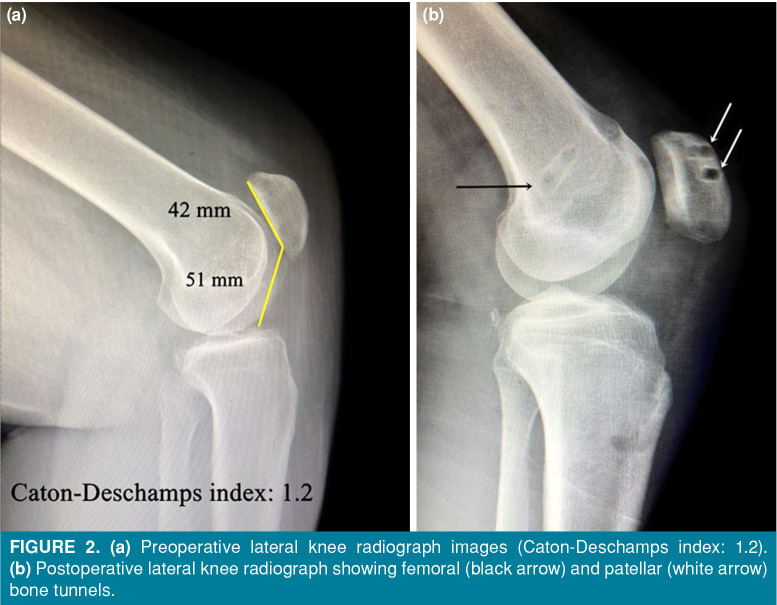

Patients and methods: Between January 2011 and January 2020, a total of 34 patients (19 males, 15 females; median age: 15.6 years; range, 13 to 17 years) with RPD who underwent anatomic MPFL reconstruction were retrospectively analyzed. Lateral release was performed as indicated. Clinical outcomes were evaluated preoperatively and at the final follow-up using the Visual Analog Scale (VAS), Lysholm, Kujala, and Tegner activity rating scales. Magnetic resonance imaging was performed to detect concomitant injuries such as bone, cartilage, and soft tissue injuries.

Results: The mean follow-up was 5±2 years. All postoperative knee functions and activity levels were statistically significantly improved without re-dislocation (p<0.001). There was no statistically significant relationship between the presence and location of cartilage lesions and clinical outcomes (p>0.05). Patients with cartilage lesions had a significantly higher CatonDeschamps index and a higher incidence of bone edema in both the patella and femur than patients without.